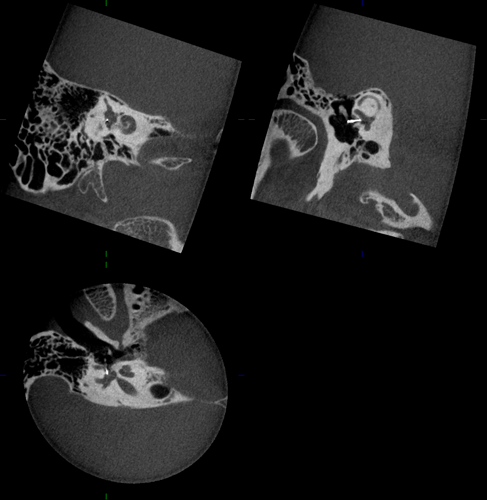

Ambossarrosion mit Stapesprothese Stapesprothese Teflon (Causse) PORP auf Stapes PORP Titan auf Stapes PORP PORP Titan disloziiert Otosklerose Otoskleroseherd TORP Pauke nicht belüftet TORP unter Knorpelinsel disl.